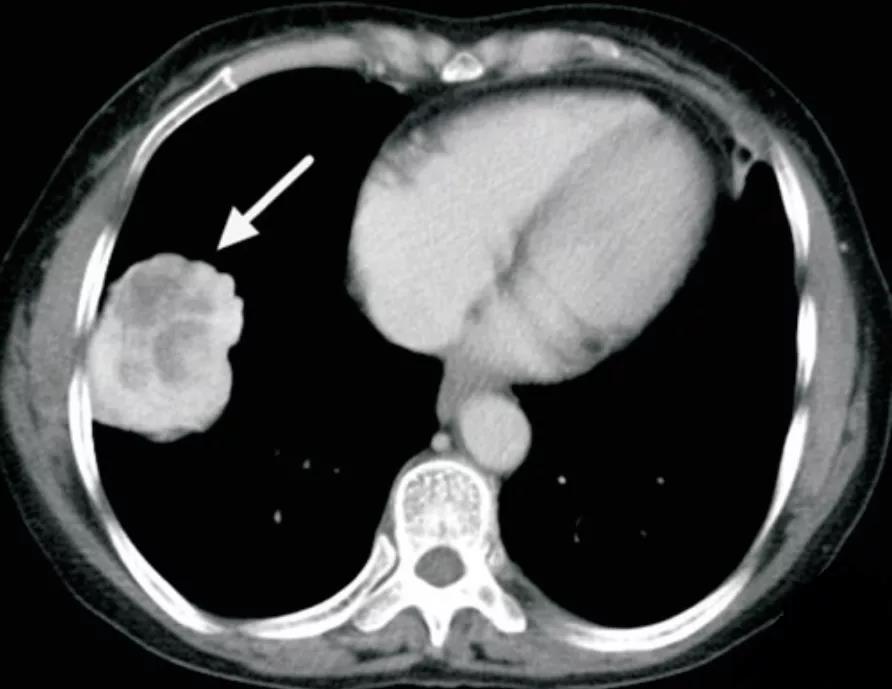

硬化性肺细胞瘤

多为单发孤立病灶,偶有多发,病灶呈圆形或类圆形,边缘清楚,密度均匀,多无毛刺,可见浅分叶,部分可见钙化、囊性变。

增强扫描病灶强化方式及程度与肿瘤成分及微血管数量相关,可表现为均匀显著强化,或不均匀轻度强化

可见特征性血管贴边征(图 2)和周围血管包绕征,即增强动脉期见病灶边缘明显强化的点状血管断面

可伴特征性尾征(图 3),即占位边缘的尾状突起,多位于近端靠近肺门一侧

另可见特征性空气新月征,上述可帮助与其他良性肿瘤及肺癌鉴别